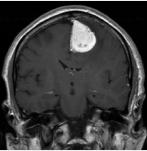

Tumoren

Behandlung von Kalottentumoren mit Kalottendefektdeckung